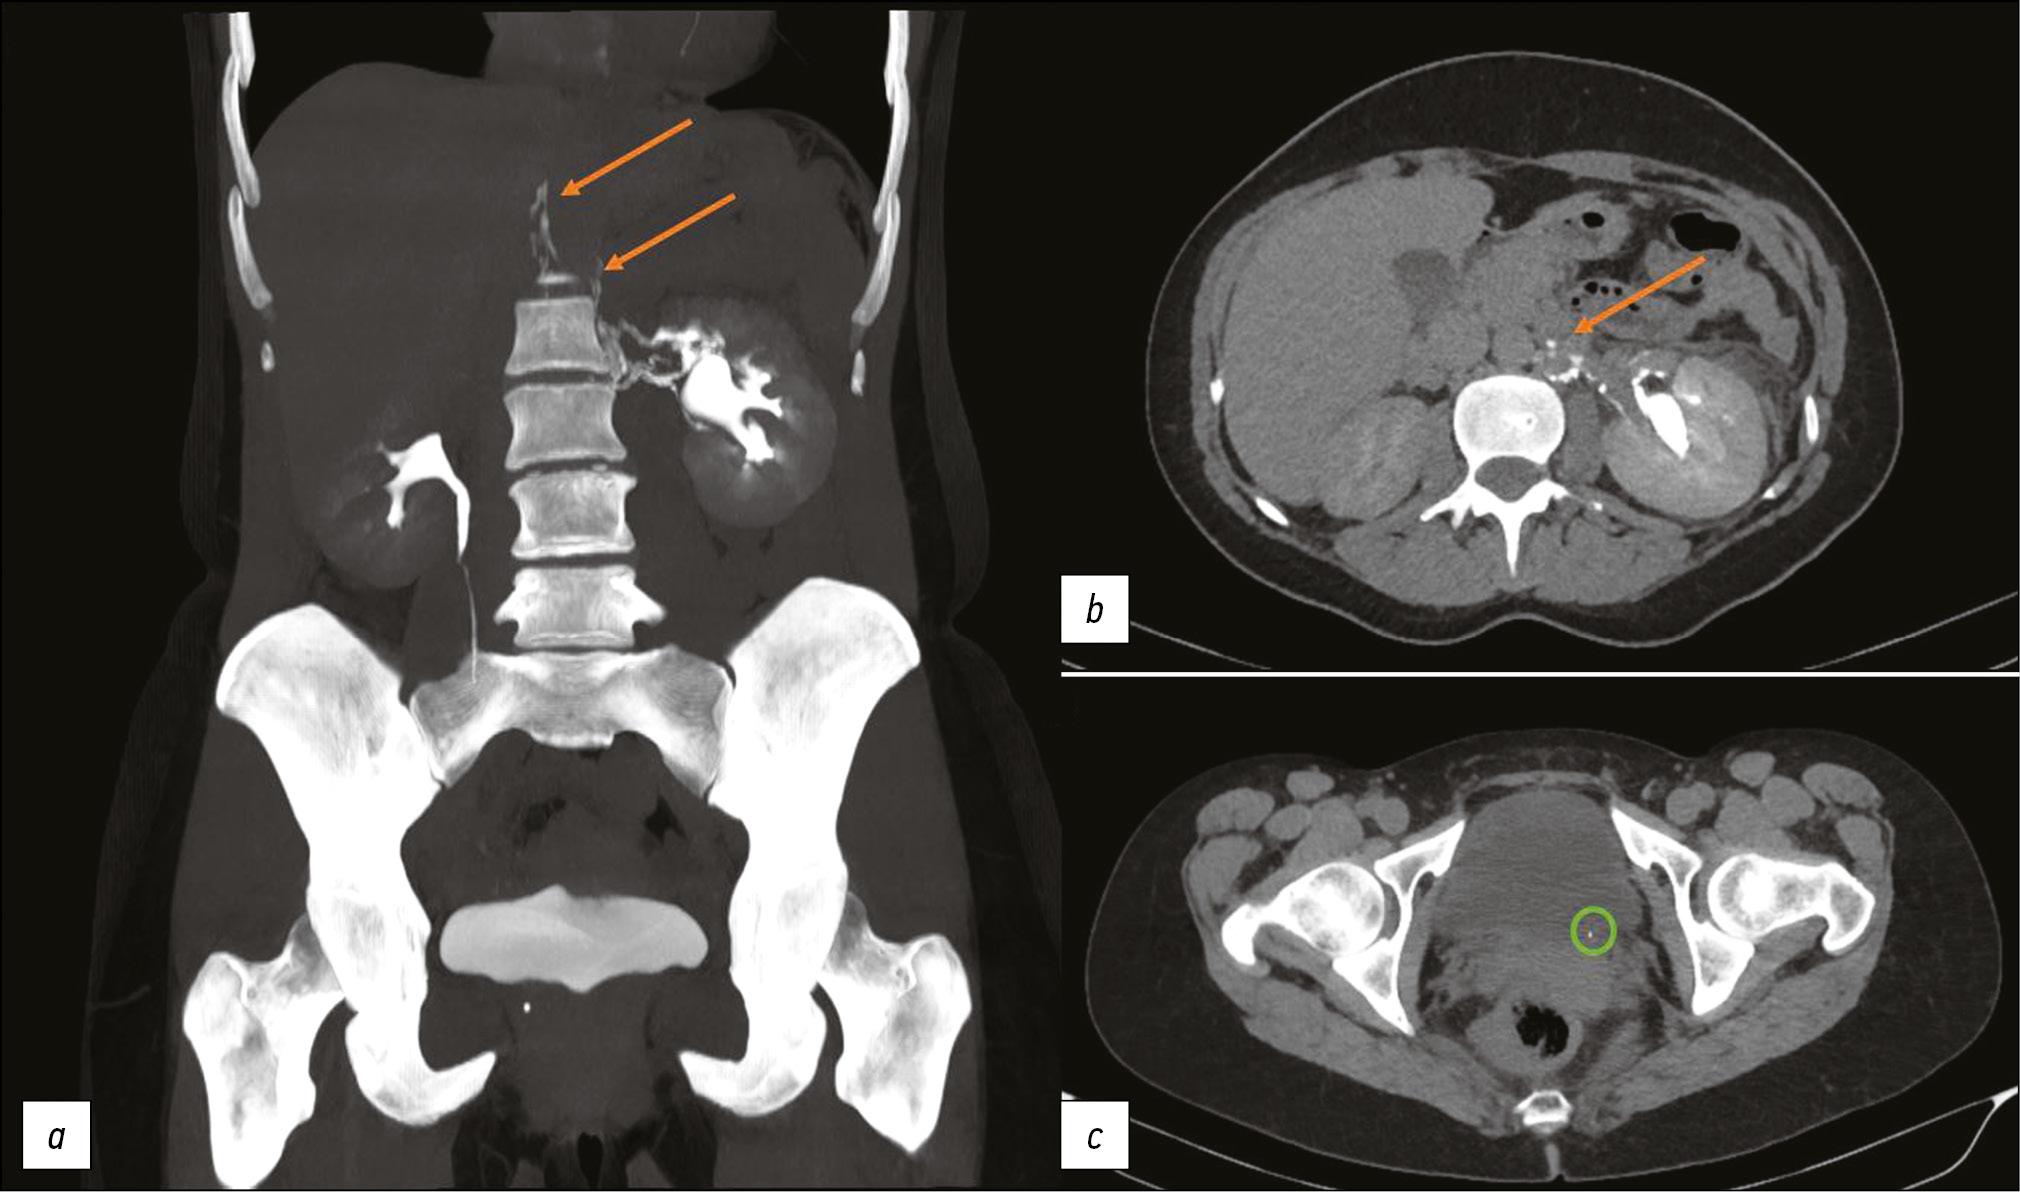

This article presents two clinical observations of uro-lymphatic fistulas diagnosed by computed tomography. In both cases, the patients were admitted with symptoms of renal colic. Uro-lymphatic fistulas are a rare condition caused by the formation of a connection between the urinary and lymphatic systems, which is caused by, as a rule, lymphatic vessel obstruction due to parasitic infestation. Other causes may be radiation therapy, retroperitoneal trauma, and tumor sprouting. In the era before antibiotics, infectious processes such as xanthogranulomatous pyelonephritis and renal tuberculosis were common. Cases of uro-lymphatic fistulas formed against urolithiasis background are presented below. In the clinical cases presented, urine directly entered the lymphatic vessels through a uro-lymphatic fistula detected on contrast-enhanced computed tomography. Uro-lymphatic fistulas caused by impaired urine outflow due to blocked urinary tract are rarely detected since abdominal ultrasound is the diagnostic method of choice in renal colic. In the vast majority of cases, uro-lymphatic fistulas are treated conservatively and do not require surgical intervention. As a rule, the formed fistulas cease to exist when its root cause is successfully treated.